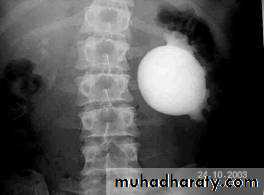

US: pre- and post-natal.IV Urography

Antenatal US Detection.Abdominal mass